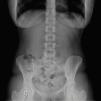

A 19 years-old female patient was admitted to the emergency department after accidental ingestion of a foreign body (safety pin). No relevant past medical history neither concomitant medication was reported. She had no complaints and the physical examination was normal. The abdominal radiograph showed an open safety pin in the upper left quadrant and no signs of pneumoperitoneum. An upper endoscopy with deep duodenal intubation was performed 6h after ingestion, but the pin was not seen. The patient was admitted to the surgical department for surveillance and remained asymptomatic. She was maintained on a clear liquid diet. At the fifth day of hospitalization and after consecutive abdominal radiographs performed each day, the safety pin was persistently located at the right iliac fossa (Fig. 1). Because of the suspicion that the pin was impacted at the ileocecal valve and after retrograde preparation, a colonoscopy was performed. Adjacent to the valve it was observed a free and open pin that was carefully caught by its pointed tip with a polipectomy snare (SnareMaster Olympus®, 10mm). Then it was gently removed under direct visualization (Figs. 2 and 3). The procedure occurred without immediate complications and no evidence of pneumoperitoneum in the control X-ray.